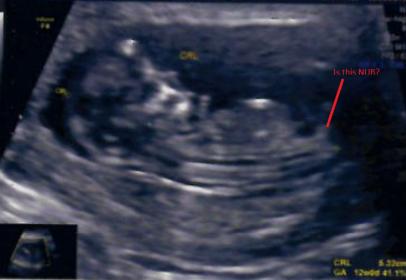

is this marked is Nub?12 W scan image

Is this marked one is male nub of 12 W

scan image?